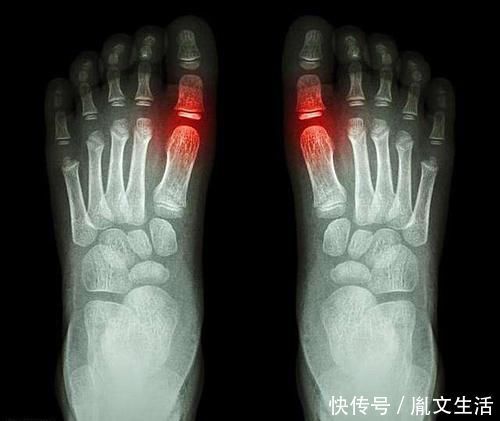

阿司匹林在内的的代谢途径与尿酸类似,长期服用可能会对尿酸排泄产生竞争性的抑制,导致尿酸升高。

不过,阿司匹林对于尿酸代谢的影响具有剂量特异性,即不同剂量的阿司匹林对尿酸影响不同:

(1)大剂量阿司匹林(>3g/d)可明显地抑制肾小管对尿酸的重吸收,促进尿酸排泄;

(2)中等剂量阿司匹林(<1~2g/d)抑制肾小管对尿酸的排泄,从而引起血尿酸水平升高;

(3)小剂量阿司匹林(75~325 mg/d)减少尿酸的排泄,轻度升高尿酸。

长期低剂量服用阿司匹林确实影响尿酸在体内的代谢,导致尿酸升高。因此,本身有高尿酸问题,又需要长期服药的患者,在服药期间一定要注意监测尿酸水平,如果尿酸出现了持续性升高,可以考虑更换为波立维(氯吡格雷)。